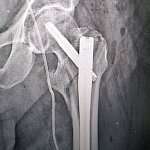

Pierwszą w historii trombektomię płucną wykonali lekarze Wojewódzkiego Szpitala Specjalistycznego w Legnicy u 75-letniego pacjenta, który trafił do SOR w ciężkim stanie po utracie przytomności i z urazem nogi. W trakcie diagnostyki rozpoznano u niego masywną zatorowość płucną, czyli stan bezpośrednio zagrażający życiu, dlatego lekarze podjęli decyzję o natychmiastowym zabiegu z użyciem nowoczesnego systemu Penumbra.

Masywna zatorowość płucna to stan bezpośrednio zagrażający życiu, wymagający natychmiastowych i zdecydowanych działań. W tym przypadku, wobec nieskuteczności leczenia zachowawczego, zdecydowaliśmy się na wykonanie trombektomii płucnej z wykorzystaniem systemu Penumbra. To małoinwazyjna metoda, która pozwala na szybkie usunięcie materiału zatorowego i natychmiastową poprawę parametrów krążeniowo-oddechowych – mówi dr hab. n. med. Piotr Rola, profesor Politechniki Wrocławskiej, kierownik Kliniki Kardiologii.